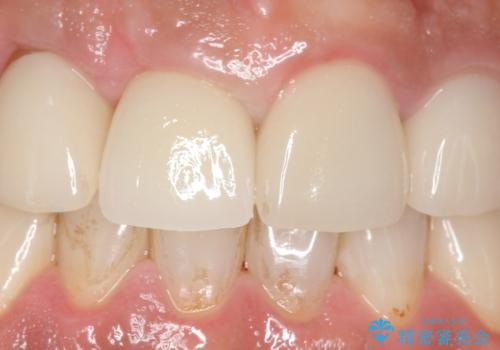

- 右上の前歯が土台ごと外れたといらっしゃった方の症例です。

ファイバーコアという土台から建て直し、咬み合わせに十分注意した上で、オールセラミッククラウンによる補綴を行いました

今回用いたオールセラミッククラウンはジルコニアフレームという白い素材の上にセラミックを盛っているため、審美性が非常に高いのが特徴です。

また、ジルコニアは人工ダイヤモンドの材料にも使われているほど高い強度を持っており、そのためオールセラミッククラウンは審美性だけでなく、奥歯やブリッジの補綴も可能とするクラウンです。